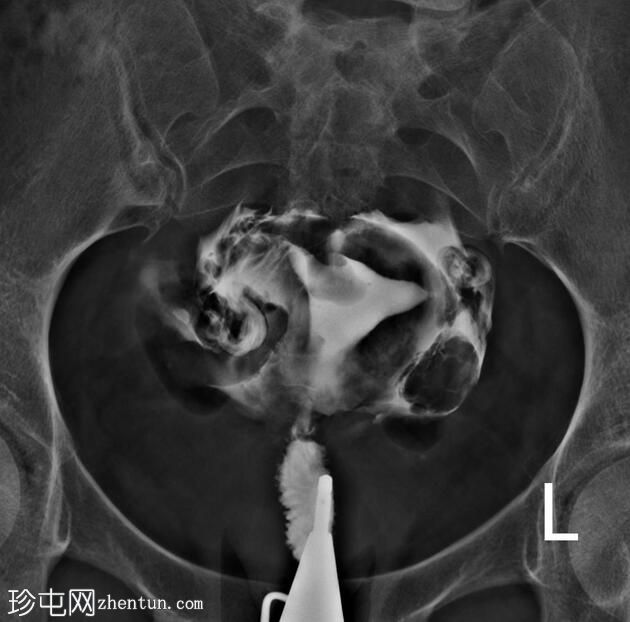

正位片

子宫内膜腔内可见一卵圆形充盈缺损,边缘光滑,强烈提示子宫内膜息肉的存在,生理盐水灌注子宫声学造影(未显示)证实了这一诊断。

鉴别诊断中还应考虑黏膜下肌瘤。